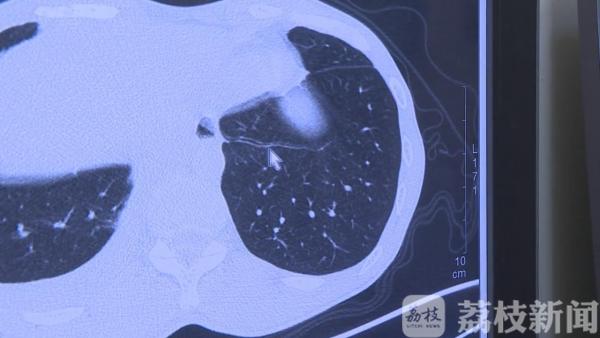

南京鼓楼医院集团宿迁市人民医院感染科副主任医师赵海燕介绍:“在他的肺上面能找到吸虫的一些典型的隧道,就确诊了是肺吸虫病,汇报了疾控中心。”